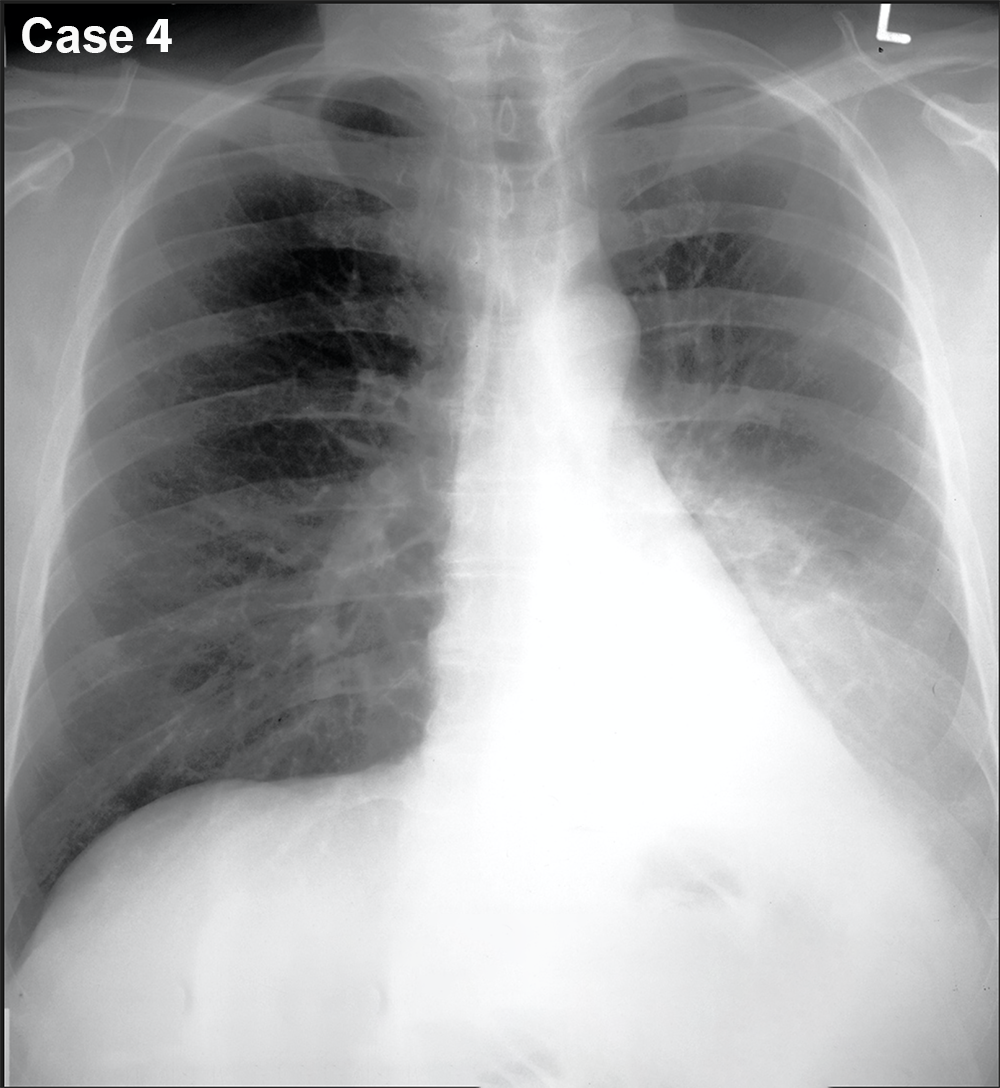

You are given a review of the ABCDE approach to frontal CXR interpretation and five cases to preview before class.

For each of these five cases, try to identify what is most abnormal, using the ABCDE framework to organize your search. Be descriptive! Try not to jump to conclusions regarding the final diagnosis. We will discuss each case in more detail in class. You can also consider what the next imaging study should be, and can make use of the ACR Appropriateness Criteria to help in this decision. You can also search the STR website for educational materials pertinent to each case.